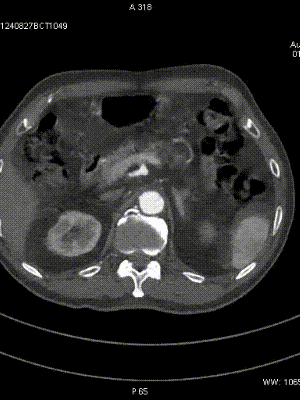

CTA:SFA-PA long CTO

Female,82 y

Severe claudication over 1 year in both extremities esp. in the left

DM over 10 years